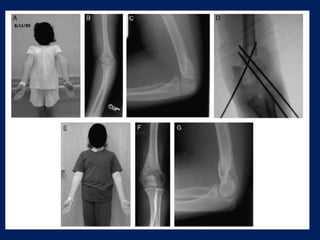

MODIFIED FRENCH OSTEOTOMY

 modifications of French’s osteotomy appears to fulfill

these criteria.

 The procedure is easy and,

 There is minimal dissection, and little possibility of

nerve damage.

 By operating with the arm in the extended position,

the adequacy of the correction can be seen during

operation and, if necessary, adjusted.

 The capacity for remodelling is reduced in the older

child undergoing osteotomy, and for this reason, the

medial “hinge” is an important feature of the

osteotomy.

 This hinge, with the screws and wire acting as a bone

suture, ensures that anatomical alignment is

maintained.

Post op management

 Postoperatively, the arm is maintained in the extended

position for two weeks.